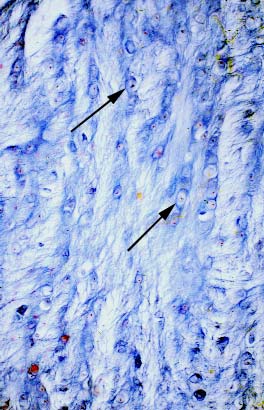

IV-19A Fibrocartilage. Note that some chondrocytes (arrows) are arranged in columns.